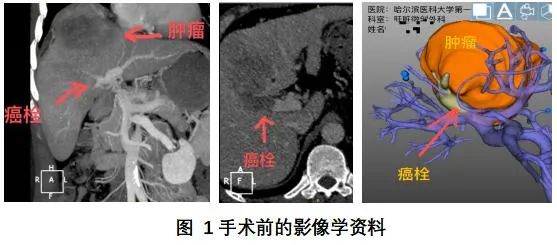

半个月前,65岁的高大伯被查出肝癌时已经是中晚期,去了几家医院都告诉他,因为瘤体较大,且生长位置不利于常规手术,只能肝移植。一家人在一筹莫展中来到了中国科学院大学附属肿瘤医院(以下简称国科大肿瘤医院),没想到找到了新的希望。 巨大肝癌患者的CT影像 高大伯是由女儿陪着来就诊的,接诊的是肝胆胰外科副主任张宇华。高大伯的女儿走进门诊时,眼睛肿肿的,一看就是刚哭过的样子,她拿出来一沓病历资料:化验单、影像学检查报告…… 来这里之前,高大伯一家跑了多家医院,得到的答案差不多:肿瘤大而且位置不好,需要切除的肝脏范围太大,剩余肝脏体积不足,无法行肝切除,建议肝移植。 “患者的右肝有两处肿瘤,最大的一处5厘米左右,紧贴门静脉右支,必须进行右半肝切除才能做到根治性切除。” 张宇华表示。 对高大伯一家来说,肝移植这个方案太渺茫,无论是治疗费用还是等候肝源,都让人感到绝望。 患者的肿瘤位于右半肝,从肿瘤切除的角度来说,可以通过行右半肝切除术来达到根治,但是高大伯的左半肝非常小,体积只有200多毫升,而术后至少需要400毫升以上才能维持人体的需要。这也就意味着,如果切除了高大伯的右半肝后,他的左半肝的功能无法满足人体需求,极有可能会造成肝功能衰竭、死亡的风险。 但是经过仔细的阅片后,细心的张宇华发现高大伯还是有手术的机会,张主任想到了一种快速使肝脏增大的技术,叫做联合肝脏离断和门静脉结扎二步肝切除术(ALPPS)。 通俗地来讲,这种手术方法就叫做“二步肝”。 简单来说,就是通过第一次开腹手术把肿瘤侧肝脏的门静脉结扎、再离断肿瘤侧与健康侧肝脏之间的肝实质,把两者之间的交通支离断。 也就是通过一定的手段,将有肿瘤的右肝和左肝“分离”。 经过这个操作后,肝脏的血流主要流向了健康侧的肝脏,也就是左肝,左肝快速长大后,达到手术要求,可以再次开腹手术切除病变侧肝脏。

术前三维重建影像

高大伯办理住院手续、进一步检查后,张主任团队精确的计算出他剩余左肝体积至少需要410ml,也就是说患者的肝脏至少需要增加200ml,才可以实施手术。

经过3周的休养,高大伯再次住院,经复查CT和三维重建,张宇华发现老高的剩余肝脏体积增加到了510ml,也就是说完全达到了手术的要求。